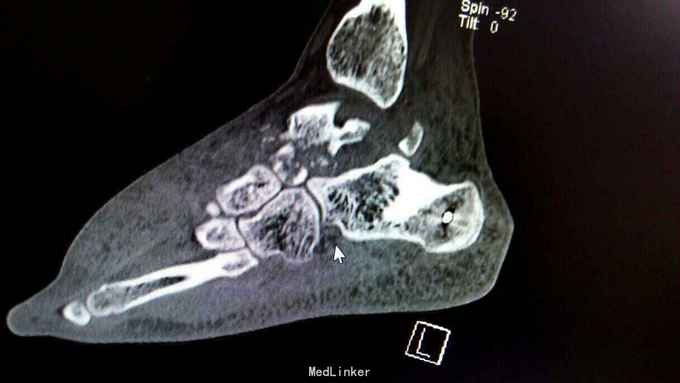

距骨骨折并脱位

重物砸伤左足疼痛畸形14小时。

左踝至中足肿胀,左足内翻畸形,皮肤可见少许细小水泡,压痛,足背动脉搏动可,足趾活动可,感麻木。

距骨骨折并脱位 入院行闭合手法复位失败,予以跟骨牵引5天,石膏外固定3天,皮肤水泡、肿胀消退后行,距骨骨折脱位切开复位内固定+距舟关节融合。术后支具外固定,勿负重3个月。

延期复位对距骨血运影响?距骨后缘骨折块不处理对踝关节影响如何?